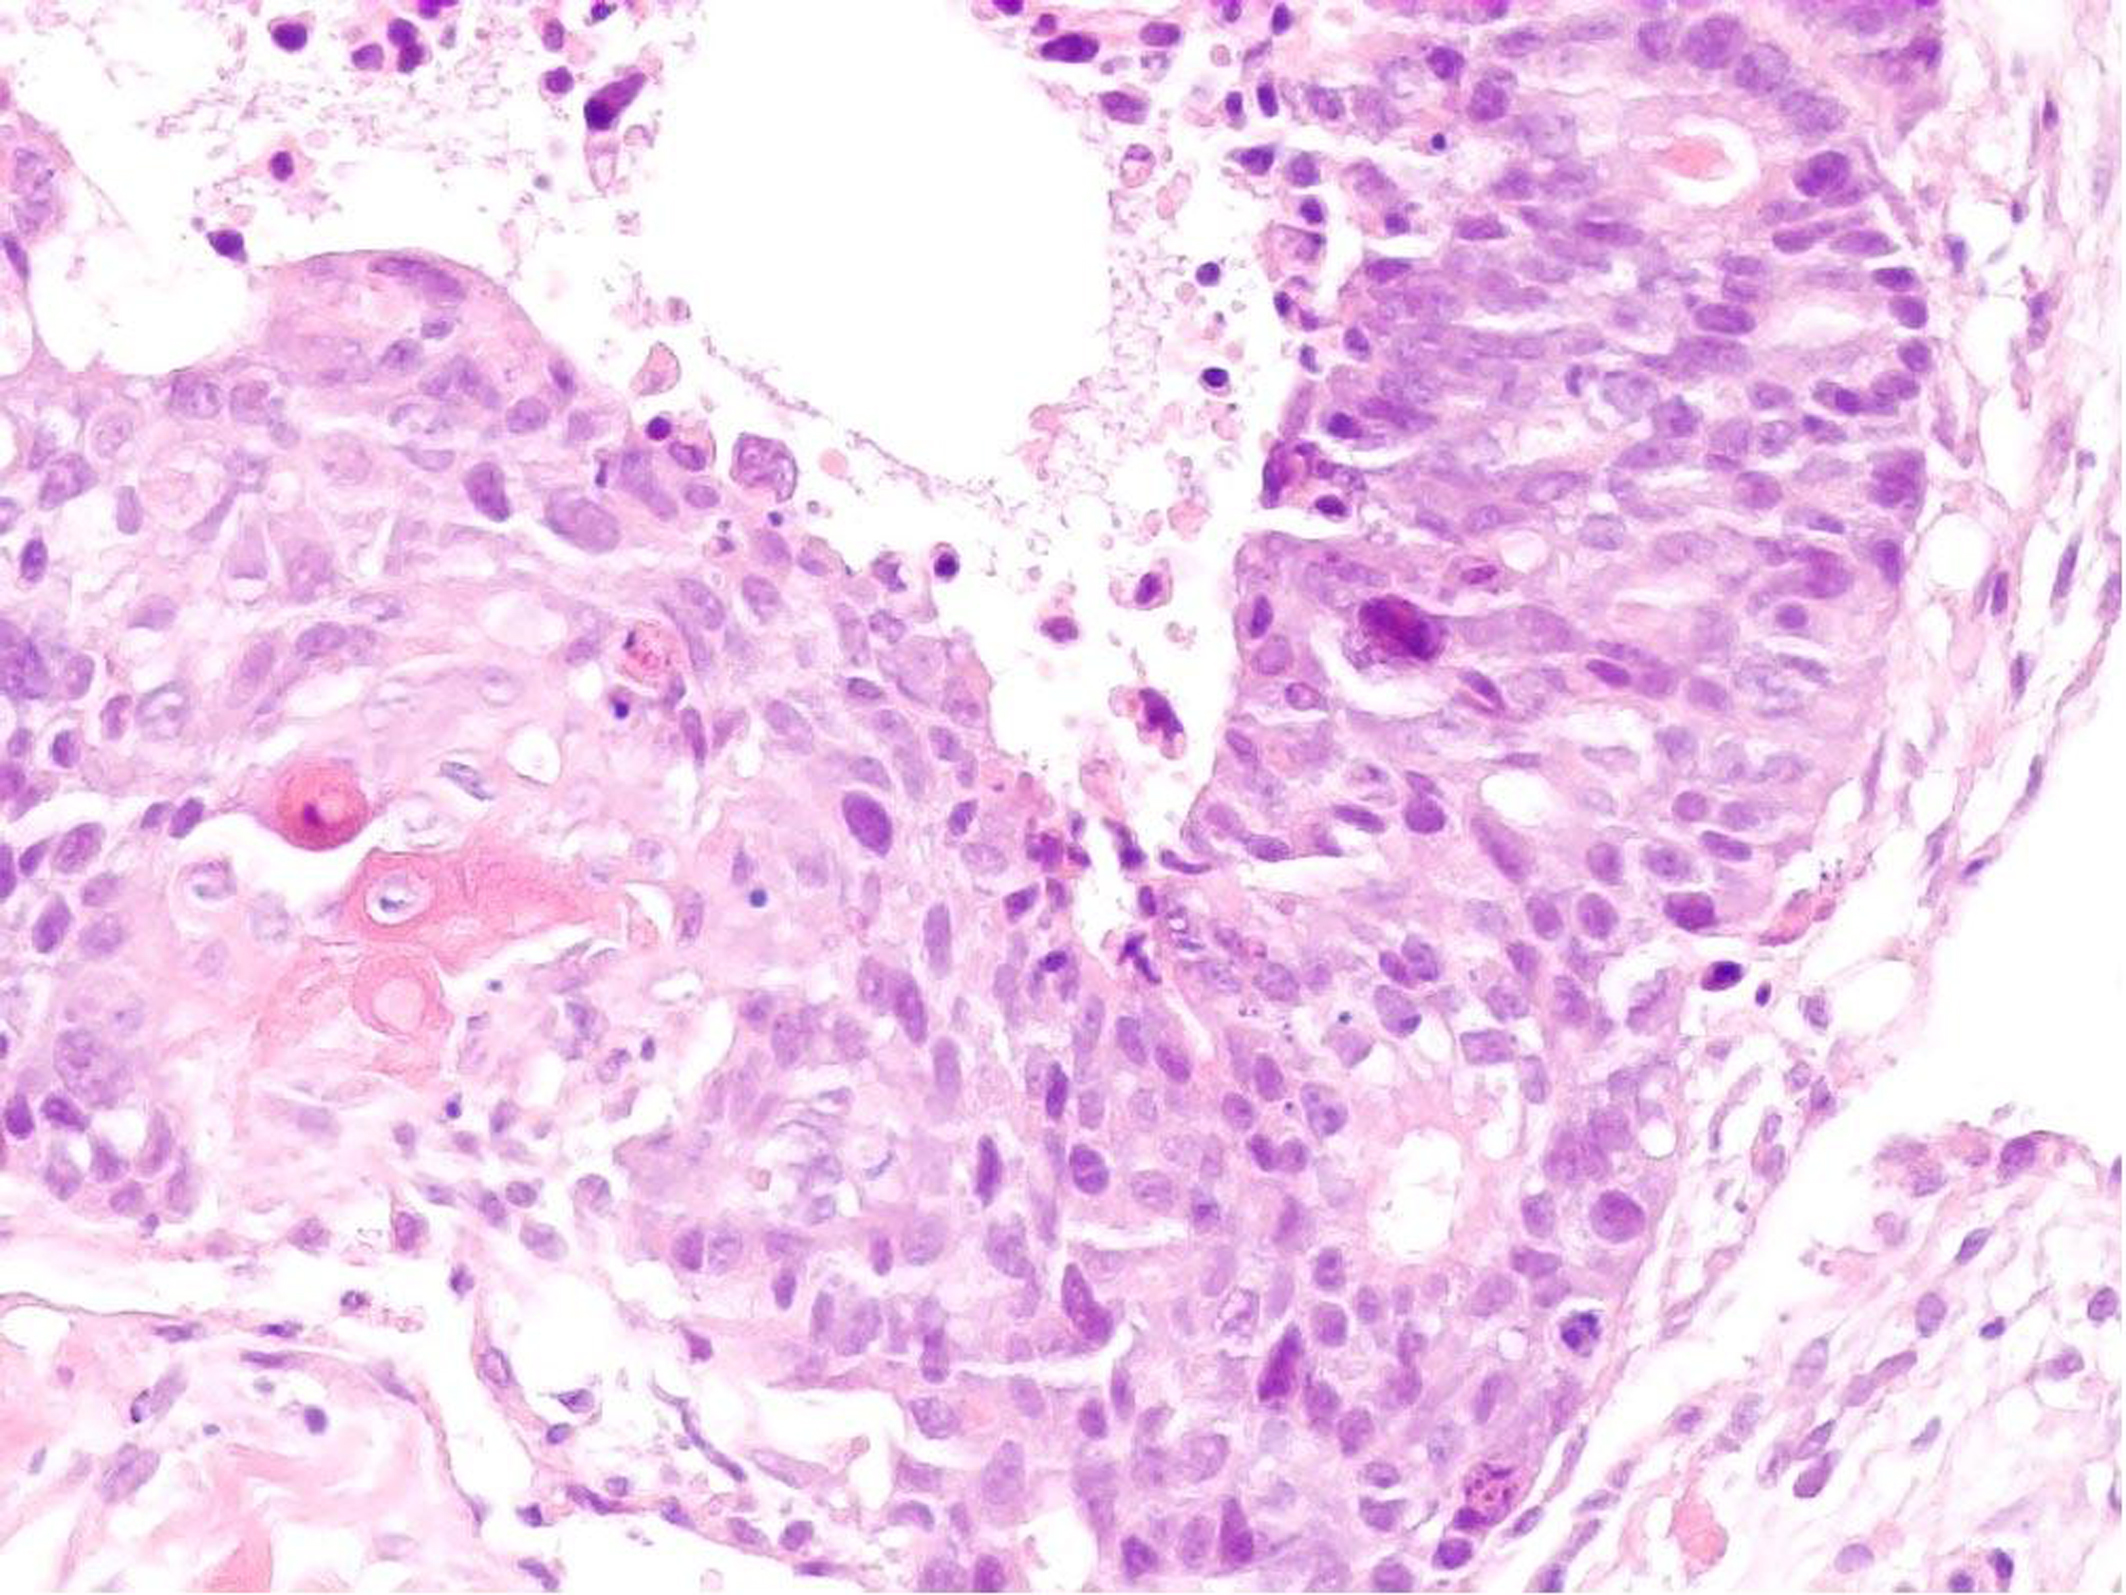

An ultrasound scan of the abdomen wall demonstrated a complex mass lying within the fatty layer. The lesion extended to 3.5 cm in diameter with a central lobular, heterogenous portion surrounded by fat, which demonstrated marked internal vascularity on Doppler study. This was suspicious of liposarcoma, and 3 core biopsies of the lump were taken which revealed extensively necrotic moderately to poorly differentiated carcinoma. There were both glandular and focal squamous differentiation histologically with keratinisation. Figure 1 illustrates histology from the core biopsy obtained from this abdominal wall lesion. The photomicrograph shows part of a malignant epithelial tumour exhibiting both squamous (left side) and glandular (right side) differentiation. Immunohistochemistry showed focal expression of cytokeratin 20 and a rare cell showing cytokeratin 7. TTF1 (a marker of primary thyroid and non-small cell lung carcinoma), oestrogen receptor and neuroendocrine markers was not expressed. At this stage, the differential diagnosis included a primary skin adnexal carcinoma, for example, a sweat gland carcinoma; however, the histology did not show the classical pattern of the best-recognised subtypes. Therefore, the more likely diagnosis was that of metastatic carcinoma with a number of potential primary sites. A computed tomography (CT) scan and upper gastrointestinal (GI) endoscopy were therefore arranged.

![]() Click for large image | Figure 1. Core biopsy of anterior abdominal wall lesion. H and E stain (x 200). |